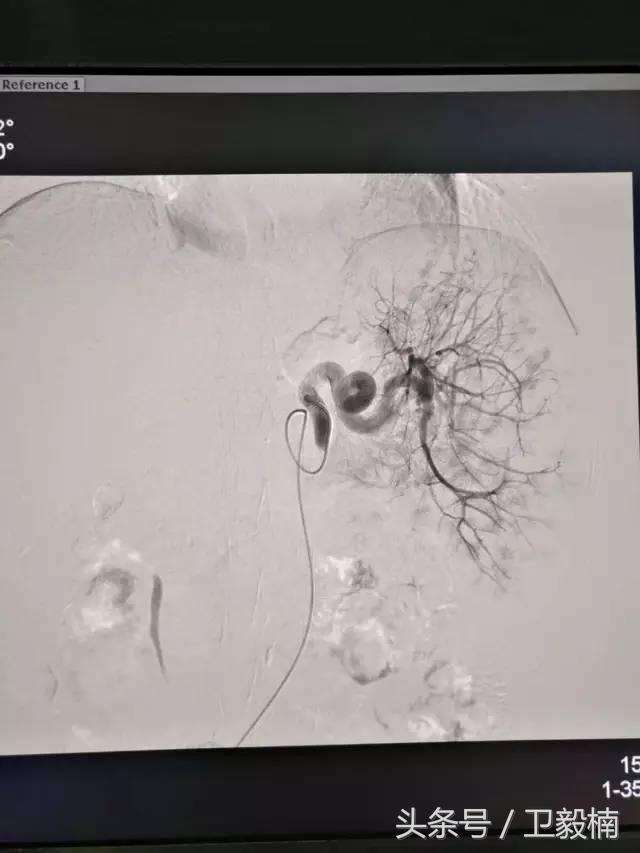

2、经导管血管栓塞法(Transcatheter embolization)

经原血管造影的导管或特制的导管,将栓塞物送至靶血管内,一是治疗内出血如外伤性脏器出血、溃疡病、肿瘤或原因未明的脏器出血。另一是用栓塞法治疗肿瘤,因肿瘤循环部分或全部被栓塞物阻断,以达控制肿瘤之生长,或作为手术切除的一种治疗手段;亦可用于非手术脏器切除,例如注射栓塞物质于脾动脉分支内,即部分性脾栓塞,以治疗脾功亢进,同时不影响脾脏的免疫功能。

常用的栓塞物质如自体血凝块、明胶海绵、无水酒精、聚乙烯醇、液体硅酮、不锈钢圈、金属或塑料小球及中药白芨等。